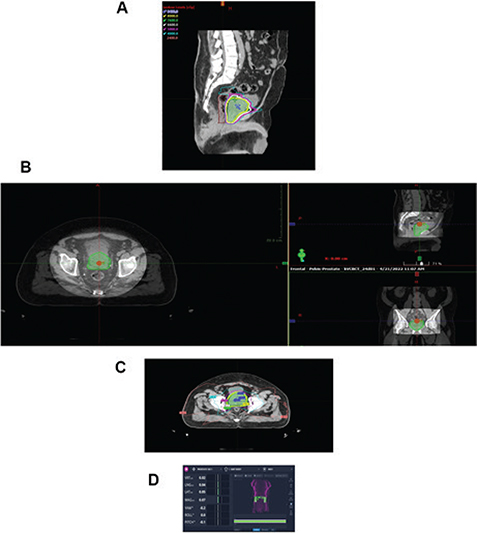

Basic science is also yielding promising results by identifying additional targets for radiation therapy. Prostate cancer cells express different adhesion molecules than normal prostate including integrins; therefore, targeting adhesion molecules in parallel with radiation therapy could provide additive cell kill in prostate cancer patients (4350). Simon and colleagues at the University of Massachusetts demonstrated that high doses of radiation were required to suppress integrin expression (one of the adhesion molecules) in prostate cancer cells and that traditional doses were less effective, implying resistance to traditional radiation therapy and indirectly supporting the utility of higher dose daily treatment that supports an argument for radiation doses similar to modern high dose stereotactic therapy (50). Wang and colleagues demonstrated that Casodex decreased adhesion properties and sensitized prostate cancer cells to radiation therapy. This would suggest that the addition of casodex or surrogate would enhance tumor cell kill with radiation therapy and possibly permit lower doses of radiation therapy to be used and generate similar outcomes. From these series of experiments, cells cloned after surviving radiation therapy have demonstrated resistance to radiation therapy after re-culture. These cells exhibit multiple phenotypic and molecular properties including epithelial-mesenchymal differentiation as well as features consistent with neuroendocrine differentiation (51, 52). Each of these areas have become important opportunities for study and we have pursued these pathways to determine if additional opportunities exist to apply alternate therapy to radiation treatment to increase tumor cell kill. Our group has been able to reverse therapeutic resistance with application of strategic molecular silencing therapy directed towards selected molecular targets (51, 52). Strategies directed to targets associated with survivin and poly (ADP-ribose) polymerise-1 (PARP-1) inhibition exhibit promise in further sensitizing prostate cancer cells to radiation therapy through multiple mechanisms including DNA repair (5357). Extracellular signal related kinases (ERK 1 and ERK 2) appear to be additional targets to sensitize prostate cancer cells to radiation therapy (5153). A series of recent experiments in our group have demonstrated interesting results relative to radiation cell kill in cells that have demonstrated resistance to therapy. Prostate cancer cell line (DU) that survived and regrew post radiation (DI) demonstrated morphologic features consistent transformation into neuroendocrine phenotype expressing neurotensin receptor 1, chromogranin B, and neuron specific enolase, unlike the parent DU cell line. In clonogenic assay, DI cells consistently demonstrate therapeutic resistance in comparison to the parent DU cell. DI cells, ERK1/2 activity is constitutively active in the resistant DI cell, less so in the DU cell. As can be seen in Figure 4, when the resistant DI cell is pre-treated with ERK 1/2 inhibitor U0126, the cells revert to the response to radiation similar to the parent DU cell. This is an exciting finding as it provides an opportunity to study possible mechanisms to therapeutic resistance and pathways to provide additional therapy to mitigate this point.

Fig 4

Figure 4. Combination therapy with radiation and ERK inhibition in neuroendocrine prostate cancer. As seen in the Western blot (a), DI (resistant) cells in a serum free medium display constitutive phosphorylation of PKC and ERK1/2, but not AKT. In figure 4b, clonogenic assay was performed with DI cells treated with and without ERK1/2 inhibitor U0126 (1 μM) 1 hr before exposed to IR with a significant improvement in cell kill when the inhibitor is applied prior to radiation therapy. (Image courtesy of the Department of Radiation Oncology, UMass Chan Medical School and UMass Memorial Health).